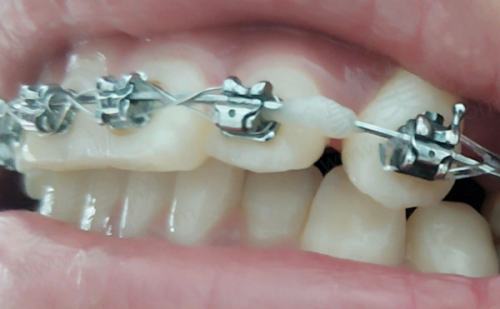

精良的设备对于口腔诊疗至关重要。天津中幸口腔医院拥有数字化口腔CT机、数字化曲面断层全景机、数字化X线机、口腔扫描仪等一系列精良设备。这些设备能够为患者提供精细、效率高、舒适的口腔诊疗服务。比如数字化口腔CT机,它可以清晰地呈现口腔内部的结构,帮助医生更正确地诊断病情。还有口腔扫描仪,能快速获取牙齿的三维模型,为后续的治疗提供严谨的数据。精良的设备不仅提高了诊疗的正确性和效率,也让患者在治疗过程中更加舒适。因此,从设备方面来看,天津中幸口腔医院处于较高的档次。

口碑是一家医院档次的更好证明。天津中幸口腔医院在患者中拥有良好的口碑,特别多患者都对它的诊疗技术、收费和服务态度给予了高度评价。患者们纷纷表示,在这里治疗牙齿不仅成效好,而且体验也非常不错。有的患者在种植牙后,牙齿修复得良好,咀嚼功能也得到了明显改善;有的患者在牙齿矫正后,牙齿变得整齐美观,自信心也增强了。这些患者的真实反馈,充分说明了天津中幸口腔医院的实力和档次。